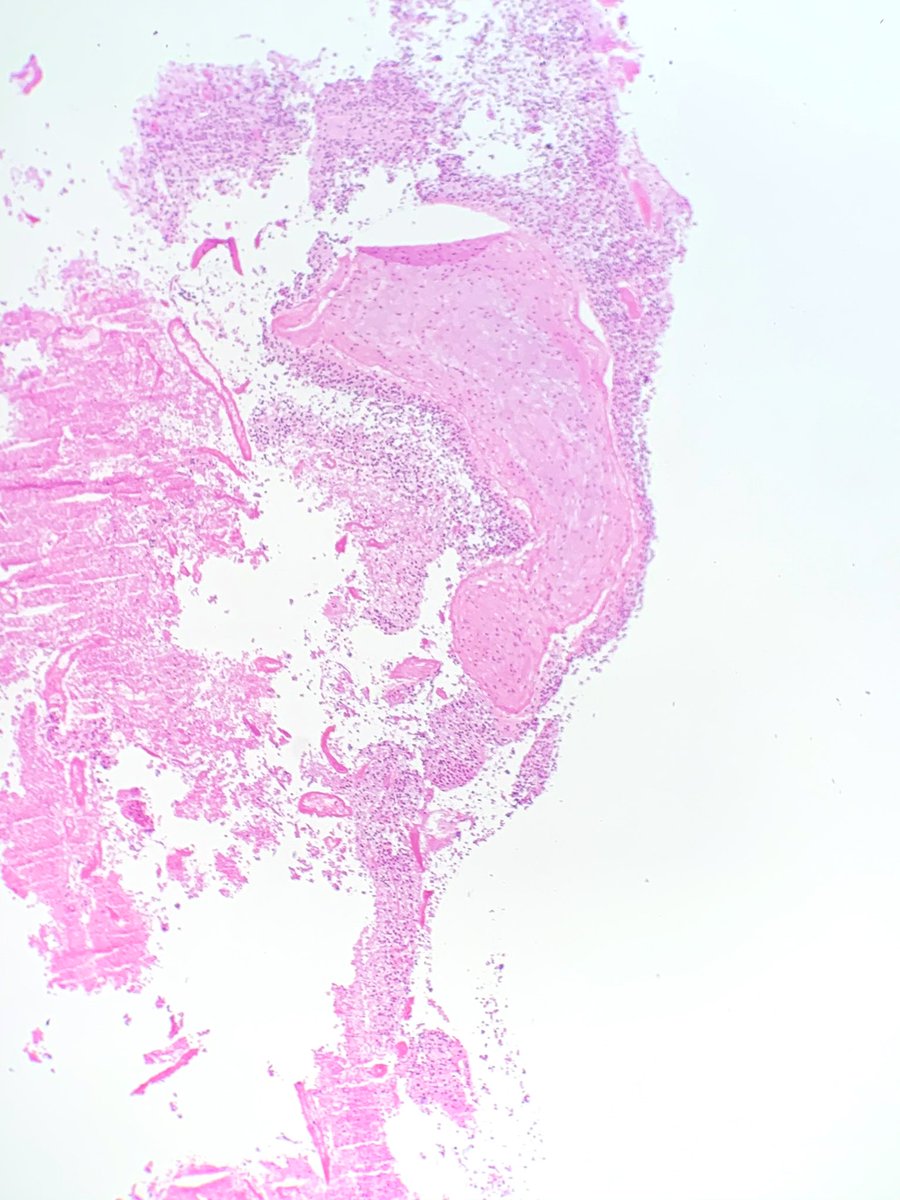

Extradural- spinal lesion in a 50 year old male. What are your differentials? Immunos to come later.

#brain#cns#pathology#neuropath#neurosurgery#surgery#neuropathology

pic.twitter.com/yjgZYV7MnL